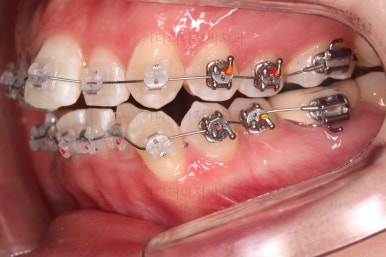

이 시점에서의 얼굴모습인데요.

확실히 삐뚤었던 치아가 가지런해지면서 입이 더 나오는 양상입니다.

이정도에서 비발치로 입을 더 넣을 수 있는지, 없는지 더 넣은 정도가 만족할 만한 수준인지 등을 중간평가 하게 됩니다.

발치교정

발치로 넘어가기로 했지만 중간평가를 자주하여 입이 너무 많이는 들어가지 않도록 하기로 했습니다.

가장 상태가 좋지 않은 치아 위주로 발치 치아를 선택했고요.

밀고 당기기를 조절하기 위해서 미니스크류도 사용합니다.